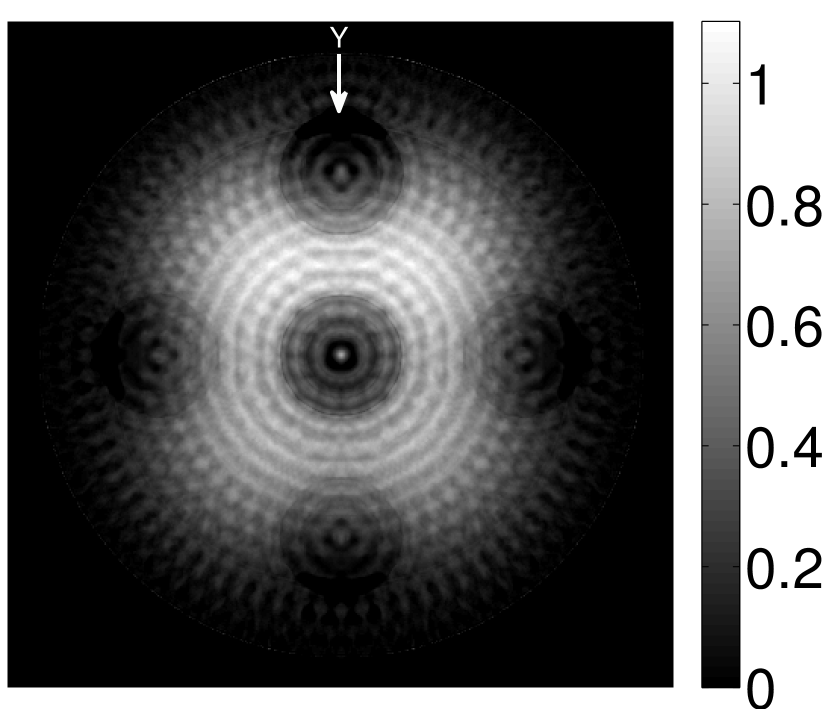

The numerical phantom shown in Figure 1(a) was employed. The phantom had a support area of mm2 and contained six uniform disks that were assigned different values of absorbed optical energy density.

A 2D circular measurement geometry was employed. transducers were evenly distributed on a ring of radius mm that enclosed the phantom. The SOS was assumed to be constant and set at mm/s. Since the simulated data were formed by use of the C-D imaging model in Eqn. (2), no inverse crime was committed. The components of this vector corresponded to equally spaced temporal samples over the interval s. Subsequently, the noiseless voltage vector was obtained by convolving the pressure data with EIR-1 in Figure 1(b).

The reconstruction region ( mm2) was represented by pixels with pixel size mm in each dimension. The initial guess of the EIR employed in the VP algorithm was different than the EIR that was assumed when generating the simulated data. This served to simulate a situation in which an experimentally measured EIR contained errors.

Figure 2(a) shows the image reconstructed by use of the conventional iterative method that utilized a system matrix based on EIR-2. Different values of the regularization parameter from the interval were considered. The reconstructed image with the value of that minimized the RMSE was chosen to represent the best performance of the conventional iterative method. Figure 2(a) and the profile in Figure 2(c) demonstrate that the use of an inaccurate EIR can result in strong artifacts and distortions in images reconstructed by use of the conventional methods.

When the VP algorithm was applied, different values of the regularization parameter from the interval and from the interval were considered. The image that minimized the RMSE was chosen and displayed in Figure 2(b). As revealed by this image and the profiles in 2(c), the VP algorithm yielded an image with fewer artifacts and distortions, and image fidelity was improved as reflected by the reduced RMSE.

The original sharp phantom shown in Figure 1(a) was convolved with a Gaussian blurring kernel to generate a smoothed phantom that possessed smaller relative spatial bandwidths. We employed the sharp and the smoothed phantoms to generate pressure data; the pressure data generated by the sharp phantom had a larger bandwidth than that generated by the smoothed one, as shown in Figure 3.

The results shown in Figure 4 suggest that the reconstructed estimates of the EIR become more accurate when the bandwidth of the is increased (Figure 4(g) and 4(h)). On the other hand, the reconstructed estimates of become more accurate when the bandwidth of the EIR is increased (Figure 4(a) and 4(b)). For a given EIR, the reconstructed estimates of that contain sharp features contain more oscillations than the estimates corresponding to the smoothed versions of . This is because more high frequency information is lost during the convolution.